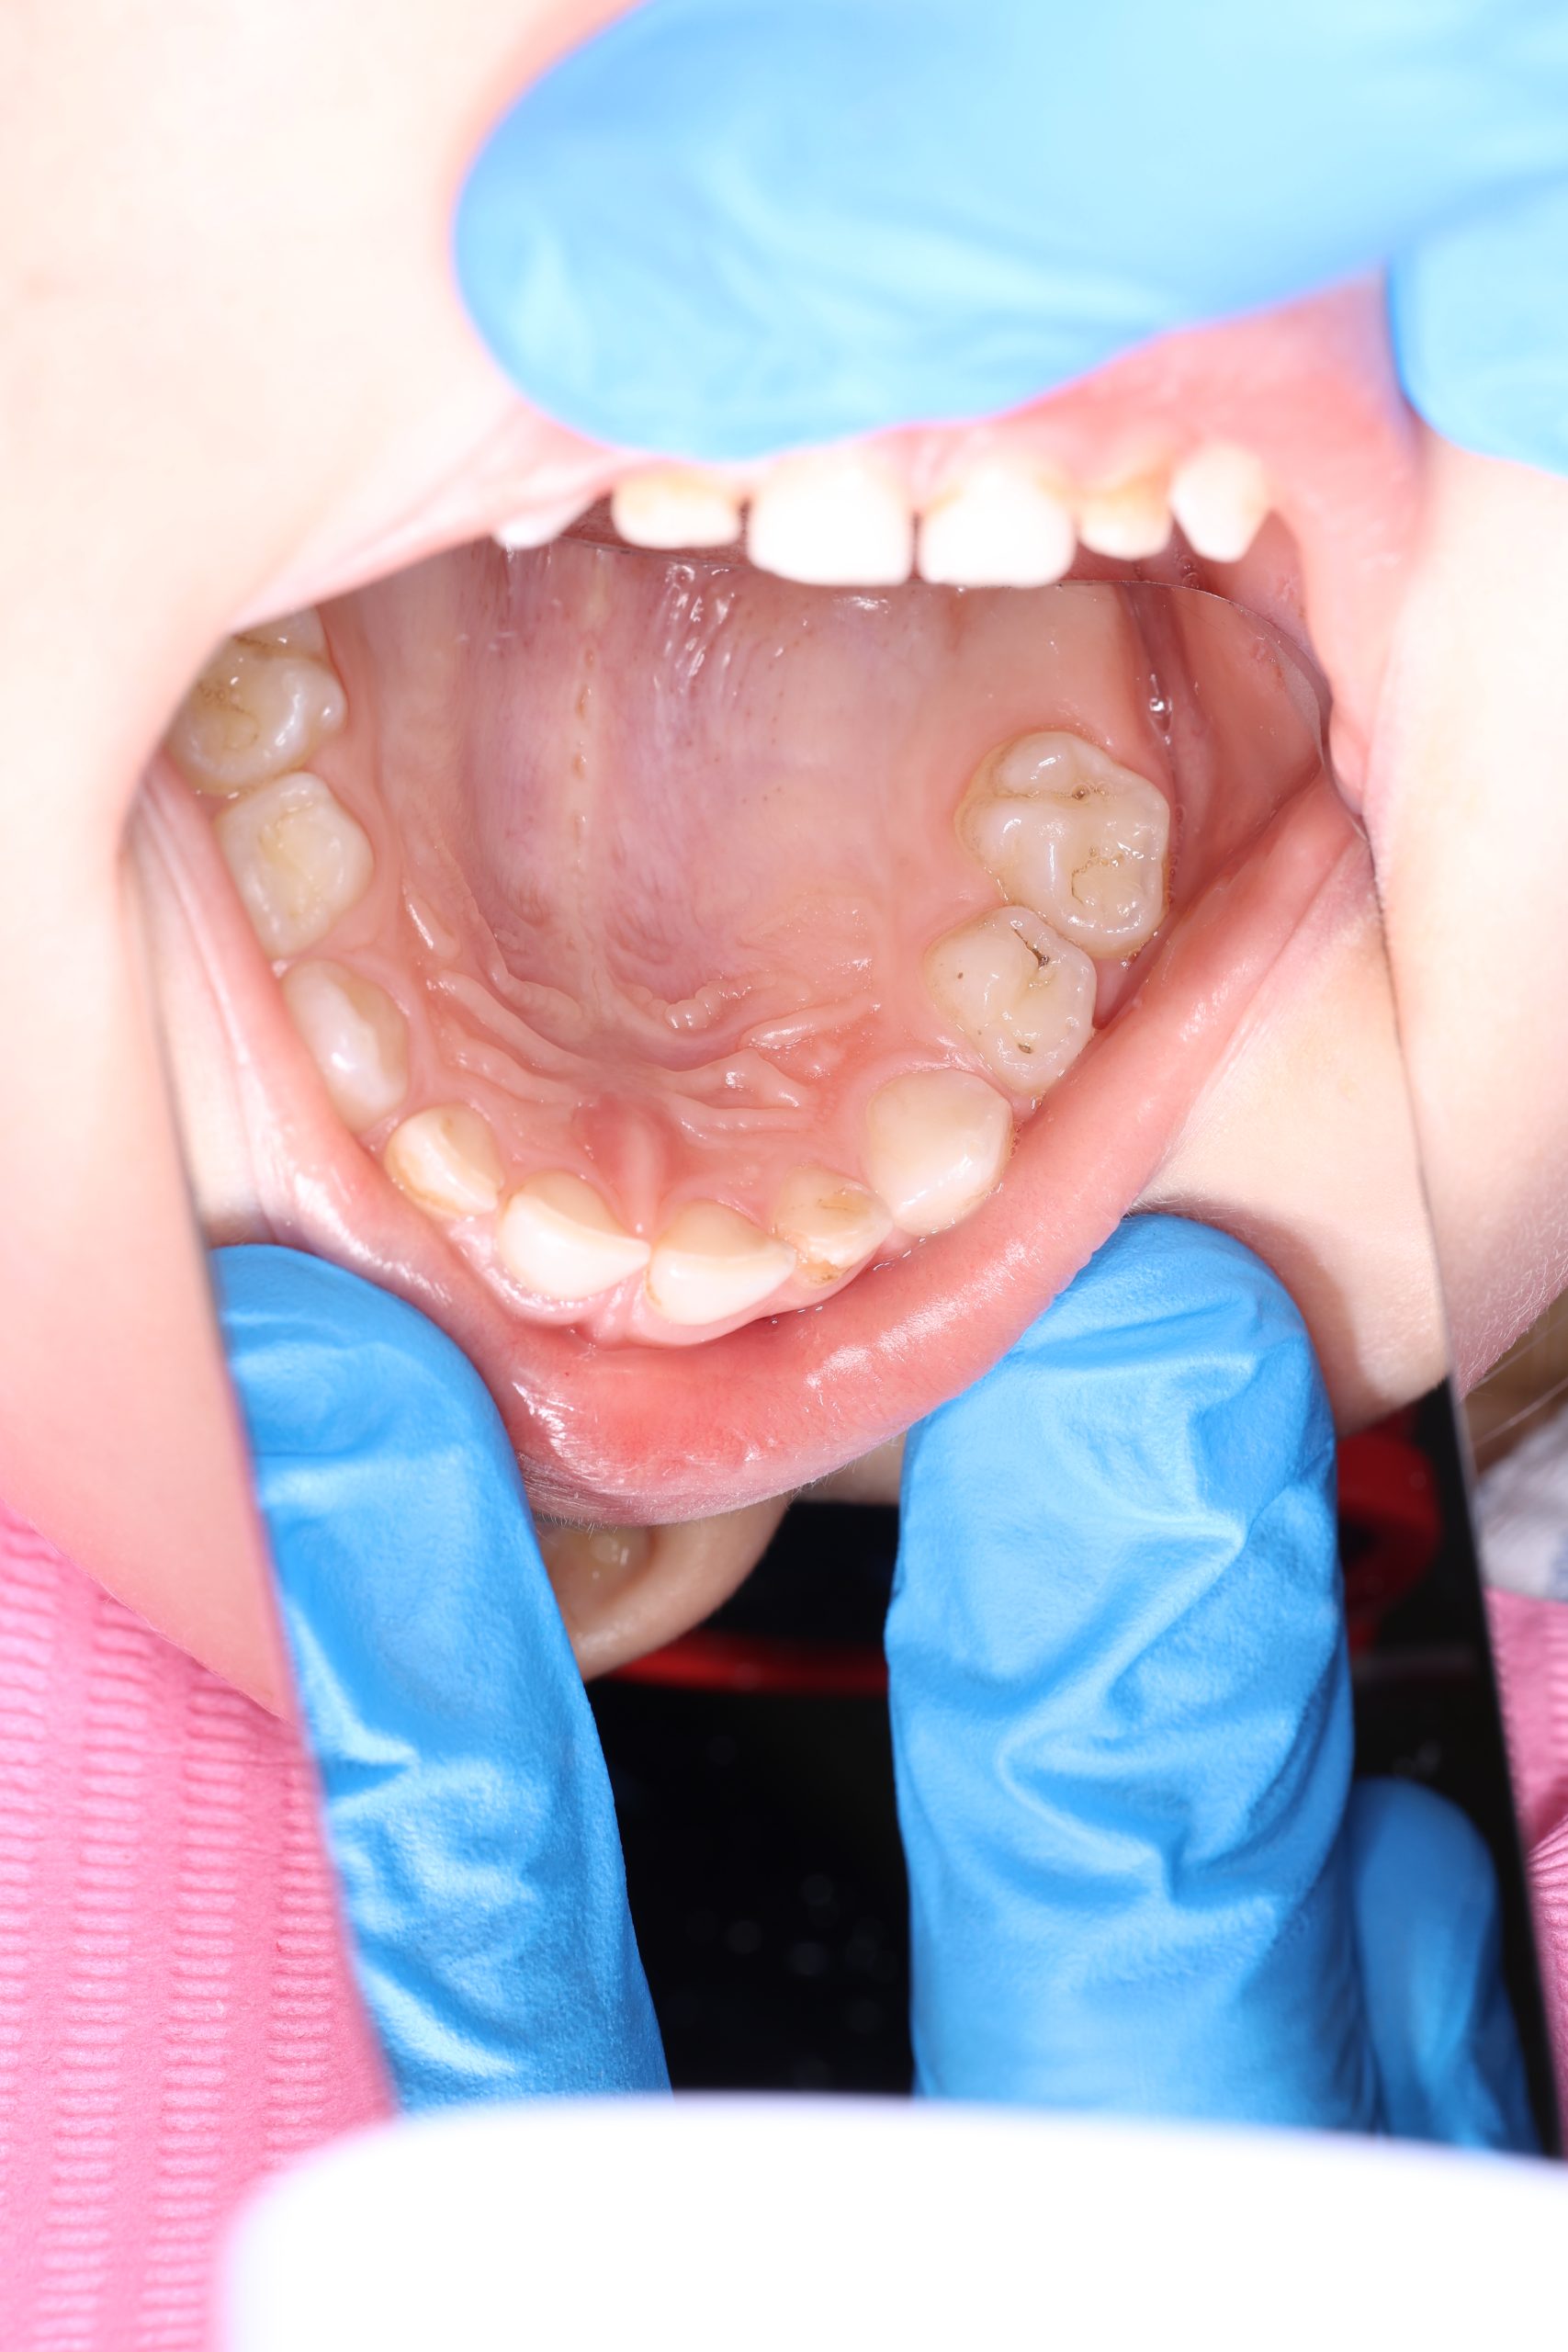

- For toddlers under 4, we provide gentle hygiene using soft rubber polishing brushes and a special tasty professional paste designed for children.

- From around age 4–5, when the child is ready, we can perform a full AirFlow cleaning using the GBT protocol.

If the child is cooperative, we perform full professional hygiene. If not, we begin with adaptive cleaning – a gentle way to introduce them to dental care and build trust.